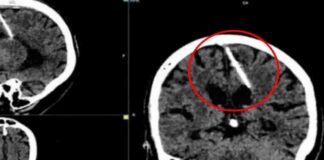

Lo que era un chequeo médico rutinario se convirtió en una pesadilla luego de que especialistas hallaron una aguja de 3 centímetros de largo...